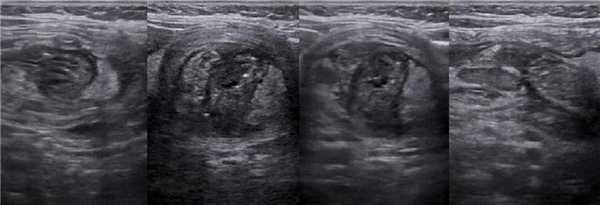

При незавершенном повороте брюшинные тяжи натянуты над 12-ти перстной кишкой и могут вызывать дуоденальную обструкцию, тогда желудок и проксимальный отдел 12-ти перстной кишки расширены. На рентгене определяются два газовых пузыря с уровнем жидкости. Полная обструкция характерна для атрезии, тогда газ в нижележащих отделах кишечника отсутствует. При незавершенном повороте чаще встречается неполная обструкция, тогда определяется газ в нижележащих отделах кишечника. На УЗИ после кормления определяют две заполненные жидкостью полости — желудок (звездочка) и проксимальный отдел 12-ти перстной кишки (стрелки).

Рисунок. Новорожденный с подозрением на высокую кишечную непроходимость. На рентгене и на УЗИ знак двойного пузыря. Во время операции определили незавершенный поворот с брюшинным тяжем над 12-ти перстной кишкой.

Рисунок. Ребенок с признаками высокой кишечной непроходимости. На УЗИ справа от средней линии живота определяется знак «водоворота». Заключение: Эхо-признаки заворота кишок.